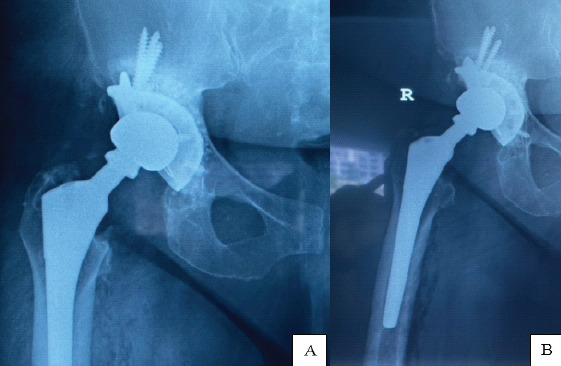

Case report: A 54-year-old woman presented with a painful right MoM hip arthroplasty. Serial radiographs demonstrated progressive migration of the acetabular shell with extensive osteolysis. After medical clearance, the patient underwent a successful isolated acetabular revision. The bone defects were filled with bone substitute, and the acetabulum was reconstructed using a metal cage and a cemented all-polyethylene cup.